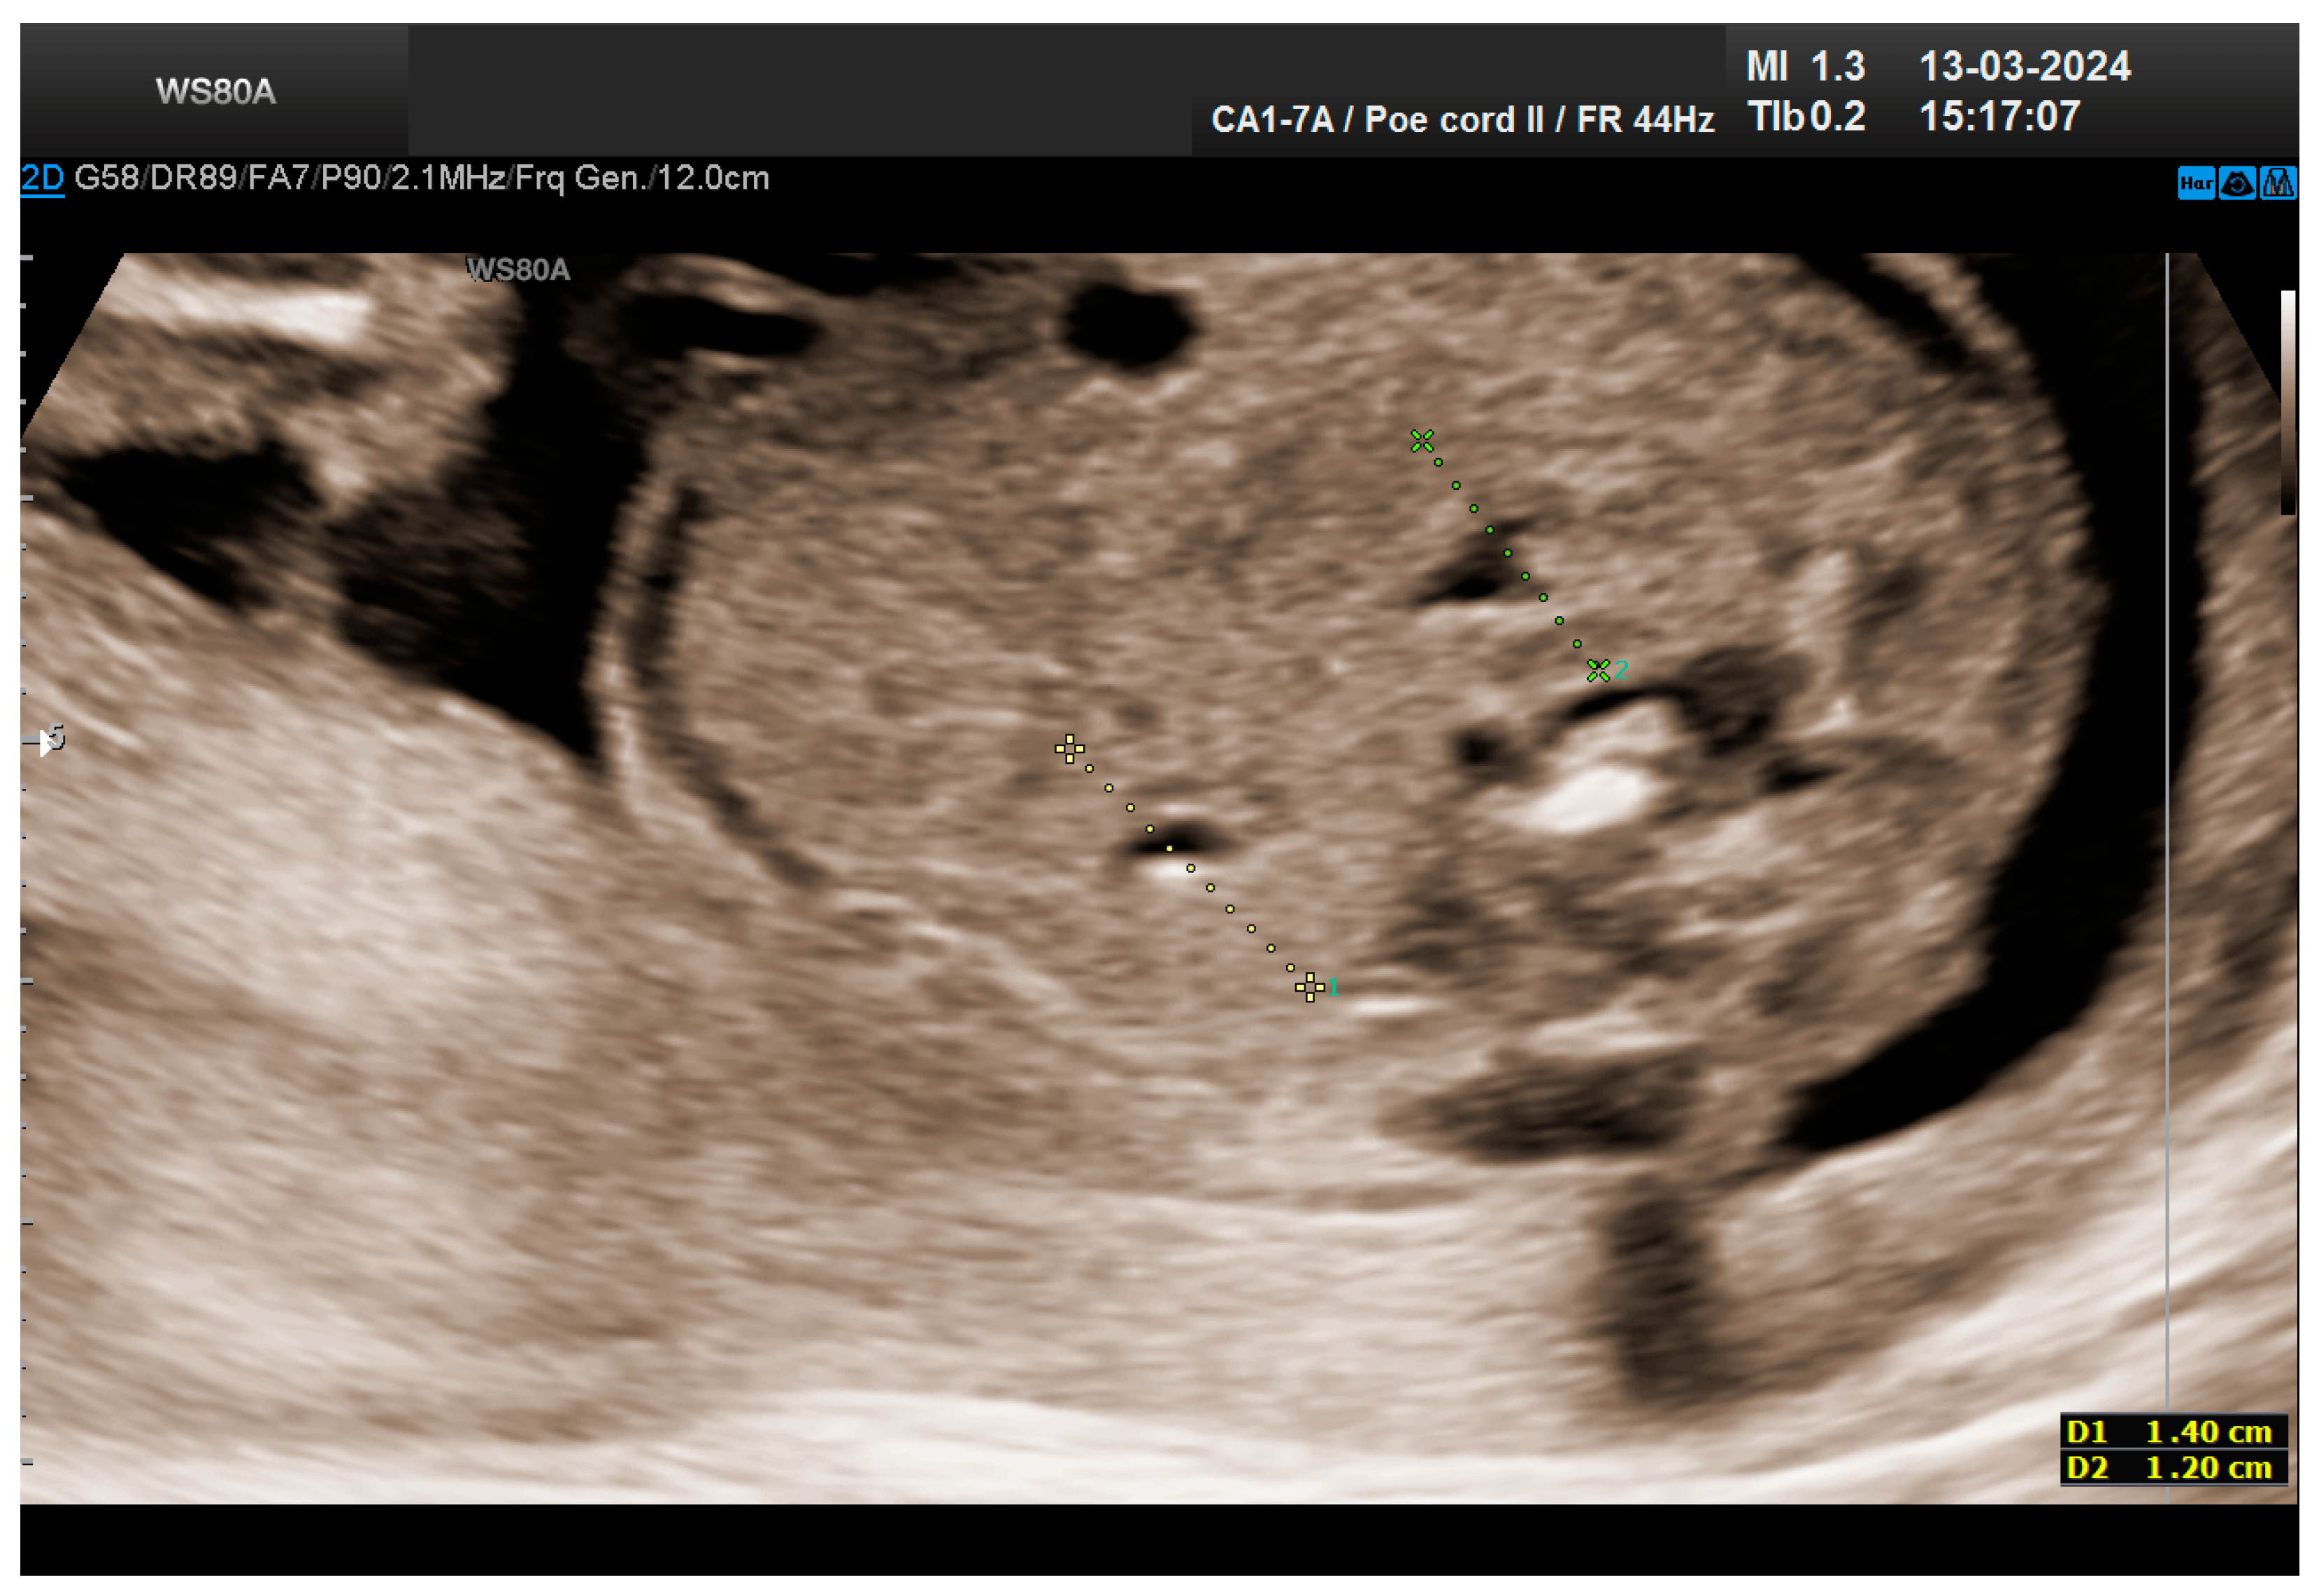

The combined test result indicated a low risk for trisomies, preeclampsia, and intrauterine growth restriction. However, during the ultrasound examination, the absence of the right renal tissue in the right parasagittal sections was noted (Figure 1). Examination of the embryo in axial sections demonstrated the presence of a relatively well-defined acoustically heterogeneous echogenic mass situated anterior to the spine, in sonographic contact with the renal tissue image correctly occupying the left lumbar fossa (Figure 2). Those aspects suggested the existence of a renal anomaly of crossed fused renal ectopia. No other embryonic anomalies were detected, the bladder image was present, and the amniotic fluid volume was normal. The calculated gestational age corresponded to the ultrasound estimate. The suspicion of crossed fused renal ectopia was maintained during a subsequent reevaluation at 17 weeks of pregnancy (Figure 3 and Figure 4).

The patient returned at a gestational age of 22 weeks for a second-trimester ultrasound screening. During this examination, the suspicion of crossed fused renal ectopia was confirmed. Axial sections revealed a normal kidney image in the left lumbar fossa and another one, anterior to the spine, without reaching the right renal fossa, fused with the normal left kidney (Figure 5). Two sources of arterial vascularization could be identified, both of them with origins in aorta as follows: one correctly originating from the lumbar aorta, serving the normally positioned left kidney, and another appearing to originate on the anterior border of aorta, at the same level, supplying the ectopic right renal tissue mass (Figure 4 and Figure 6). The bladder was present, with normal appearance and volume. No left ureterohydronephrosis was detected. The presence and course of the right ureter could not be identified. The amniotic fluid volume was normal. No other severe or minor anomalies were observed.

Figure 3. The two kidneys are clearly visualized: the right one, ectopic, fused with the left kidney, normally positioned—ultrasonography revaluation at 17 weeks.